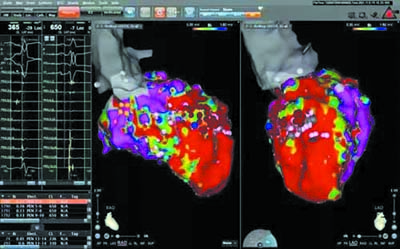

心内科立即启动急诊介入绿色通道,导管室技师、护理人员接到通知后立即顶风冒雪赶往医院,李学勋副主任医师、田洪波副主任医师也克服大雪带来的重重困难及时赶到医院,为患者在局麻下行急诊室速射频消融术。血管穿刺成功后,李学勋副主任医师迅速将标测导管送入患者心脏内,5分钟内即完成了室速的标测,然后立即对室速病灶进行放电消融,放电3秒室速即刻终止。李学勋副主任医师又对患者心脏左心室进行了详细的电生理标测检查,发现患者整个左心室前壁均发生了大面积纤维化,极易发生室速,随后将潜在的室速病灶逐一进行了消融。反复静滴异丙肾和起搏诱发,室速再未发作,手术成功,用时1.5小时。

室速病灶标测消融